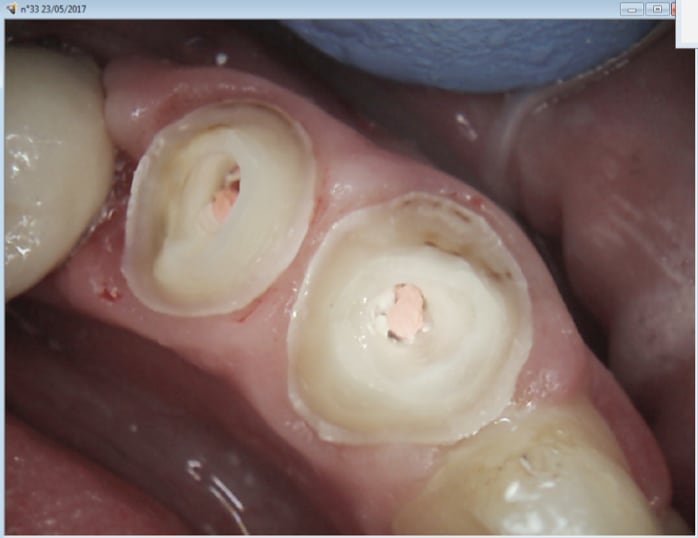

23/05/2017 à 21h07

Je vais surement passer à l'empreinte optique et au tout ceram juxta gingival.

Ras le bol de préparer en sous gingival pour les céramo metal. Perte de temps.

En effet mes loupes offrent des possibilité de tailles ultra précises sans toucher la gencive C'est un autre métier.

Capture d écran 2017 05 23 21.02 - Eugenol

Pensez vous qu'une caméra puisse digérer ce type de profondeur de limites , notamment en distal ?

A contrario la caméra peut elle scanner l'empreinte , et la rendre en positif ?